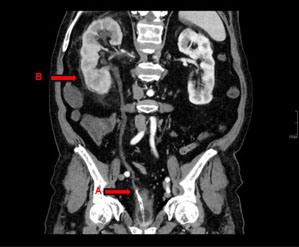

During the pre-surgical workup, a non-contrast computed tomography (CT) scan revealed stenosis in the vascular lumen of the iliac arteries and significant calcification. Angiotomography confirmed the absence of contrast below the cava cava catheter insertion site, requiring an alternative surgical plan for the patient’s first graft. The donor was his 25-year-old brother, immunosuppressive induction therapy was performed with basiliximab and steroids. On the day of surgery, the patient’s urea level was 92 mg/dL and creatinine level was 9.6 mg/dL.